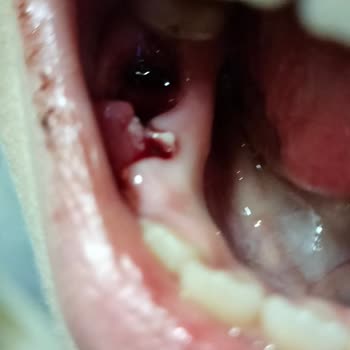

Yaklaşık dört ay önce kızımın tedavisi için Aydın Üniversitesi Diş Hastanesi’ne başladık. Tedavi öncesinde röntgenleri çekildi, yapılacak işlemler söylendi ve 4 dolgu ile diş temizliği için 12 bin tl fiyat verildi. Plak ya da tel için ise net fiyat veremeyeceklerini, 55 bin ile 75 bin tl arasında de...